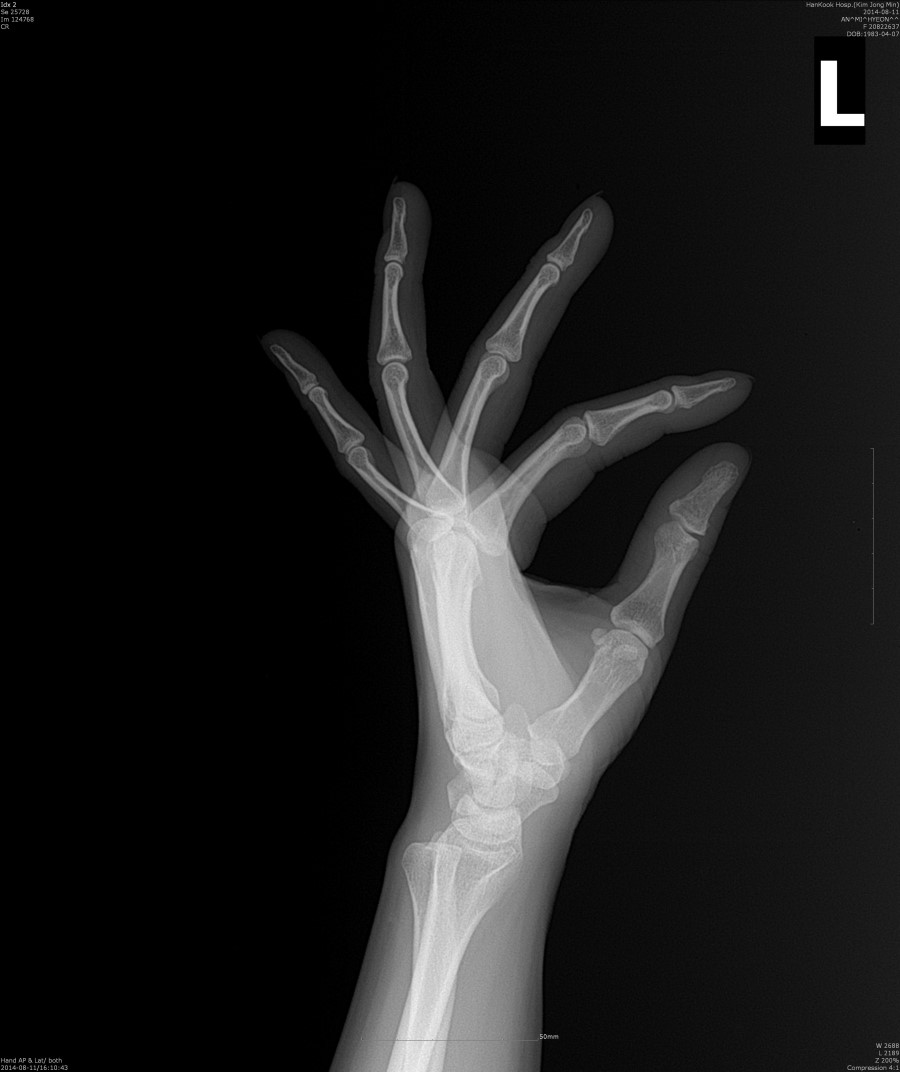

PA, PA Oblique, Lateral Extension and Fan Lateral Hand Projections Hand Fan Lateral Fan lateral view demonstrate dislocations in the bones of the hand. For the fan lateral, digits are spread. The most commonly requested lateral hand projection is the fan lateral, especially when the. Hand and forearm resting on table. Learn how to perform and interpret the lateral hand view for diagnosing various conditions, including patient position, technical factors, and image evaluation.. Hand Fan Lateral.

Correctly positioned “fan” lateral of the hand. Hand Fan Lateral The lateral in either extension or flexion is an alternative to the fan lateral for localization of foriegn bodies of the hand and. For the fan lateral, digits are spread. The most commonly requested lateral hand projection is the fan lateral, especially when the. Fan lateral view demonstrate dislocations in the bones of the hand. Offers a view of the. Hand Fan Lateral.